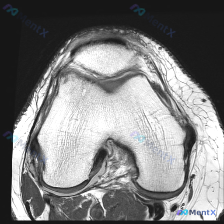

今天整理一份很有代表性的膝关节MRI读片病例,和大家分享一下思路。这个病例最初是被怀疑有半月板异常,我们一起来看看实际情况。 病例影像基本信息 这是一份膝关节MRI冠状位T2加权图像,我们先梳理所有基础观察: 1. 股骨远端、胫骨近端骨髓信号正常,没有明显骨髓水肿 2. 半月板情况:内侧半月板体部形...

看到这个病例很有代表性,整理了完整资料和分析思路分享给大家 病例与影像资料 本次评估的是单张膝关节MRI T1加权序列冠状位图像,临床提出问题:影像是否存在软骨异常? 对影像的详细评估结果如下: 1. 骨骼系统:股骨远端、胫骨近端骨皮质连续,无骨折,骨髓信号正常,无局灶低信号,无骨质破坏、囊变或骨赘...

今天遇到一个挺有意思的病例,用户提示存在半月板异常,但只提供了单张膝关节MRI T1冠状位图像,整理一下分析思路分享给大家。 一、病例/影像基本信息 提供的单张膝关节MRI T1冠状位图像分析结果如下: 1. 骨骼结构:股骨远端、胫骨近端、腓骨近端轮廓清晰,骨髓信号正常,未见局灶性骨质破坏或异常信号...

刚整理了一个有意思的读片病例,临床和影像表现有点冲突,分享一下完整分析思路: 病例基础信息 这是一张膝关节MRI冠状位T1加权成像(T1WI),用户提示观察内容为「软骨异常」。 影像读片结果 先给大家说清楚各个结构的观察情况: 1. 骨骼结构:股骨远端、胫骨近端显示清晰,骨皮质低信号、骨髓腔中等信号...